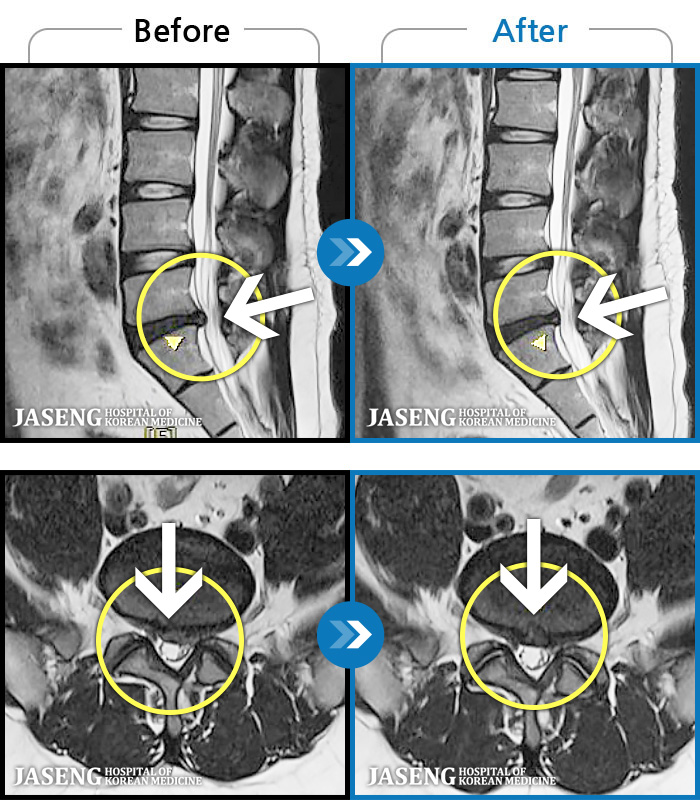

- MRI ġ

MRI ġ

1,304 MRI ũ ʸ Ȯϼ.